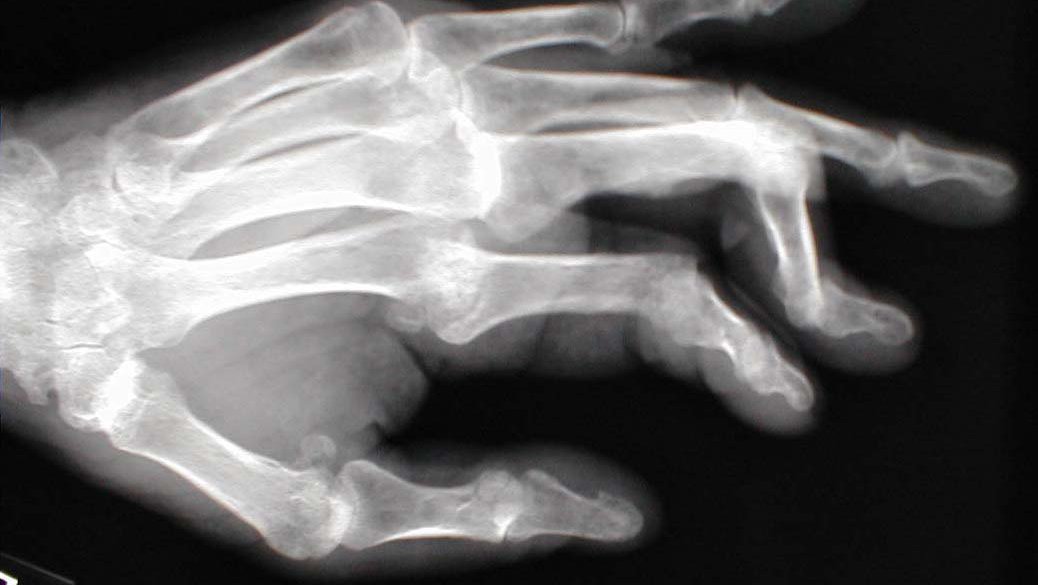

Boutonniere deformity Image How Do You Splint A Boutonniere Deformity learn about the causes, symptoms, and treatments of boutonnière deformity, a finger injury that affects the middle joint and the fingertip. Splinting alone may not give a good result in a case where the deformity. nonsurgical treatment is a splint that keeps your pip joint straight, but allows your other joints to move. Find out how splinting and. How Do You Splint A Boutonniere Deformity.